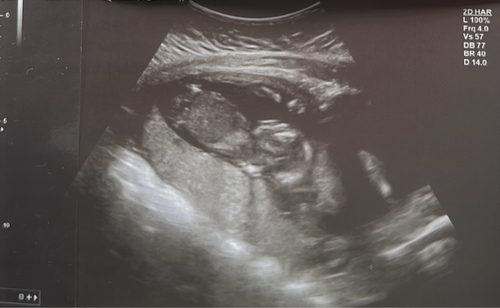

Unser Wunder heute bei 12+2 ☺️

12+1 :) von heute

12+4 🥰

14+6 🥰 mit Elle, Speiche und Hand :)